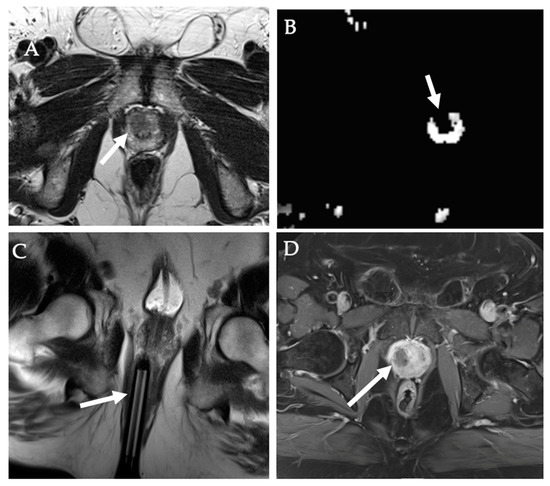

9. Prostate Tumors

- Tourinho-Barbosa, R.R.; Batista, L.T.; Cathelineau, X.; Sanchez-Macias, J.; Sanchez-Salas, R. Ablative options for prostate cancer management. Turk J. Urol. 2021, 47, S49–S55. [Google Scholar] [CrossRef]

- Linares-Espinós, E.; Carneiro, A.; Martínez-Salamanca, J.I.; Bianco, F.; Castro-Alfaro, A.; Cathelineau, X.; Valerio, M.; Sanchez-Salas, R. New technologies and techniques for prostate cancer focal therapy. Minerva Urol. Nefrol. 2018, 70, 252–263. [Google Scholar] [CrossRef]

- Natarajan, S.; Raman, S.; Priester, A.M.; Garritano, J.; Margolis, D.J.; Lieu, P.; Macairan, M.L.; Huang, J.; Grundfest, W.; Marks, L.S. Focal Laser Ablation of Prostate Cancer: Phase I Clinical Trial. J. Urol. 2016, 196, 68–75. [Google Scholar] [CrossRef]

- Walser, E.; Nance, A.; Ynalvez, L.; Yong, S.; Aoughsten, J.S.; Eyzaguirre, E.J.; Williams, S.B. Focal Laser Ablation of Prostate Cancer: Results in 120 Patients with Low- to Intermediate-Risk Disease. J. Vasc. Interv. Radiol. 2019, 30, 401–409.e402. [Google Scholar] [CrossRef]